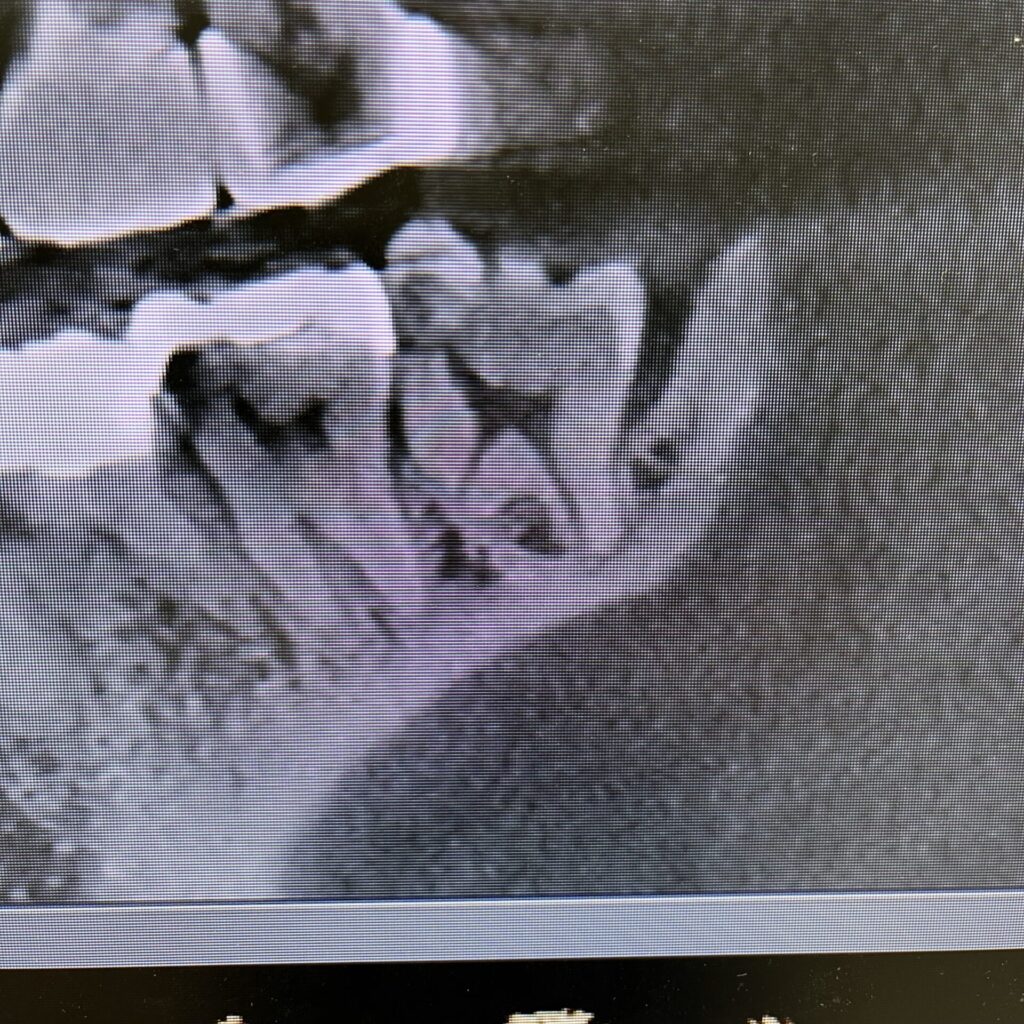

本日の親知らず(閲覧注意)

当院にて治療中の患者さんです。

親知らずに関してはいつも虫歯ですねーと言われてきたのに誰も処置はしてくれなかったとのこと。

何故虫歯なのに治療しないのだろうと思っていたとのことです。

画像がこちらです

レントゲンの形も変で、歯科医師からしたら慣れない抜歯、不安も覚える方も多いでしょう。

そこで口腔外科医師の出番です。

抜歯するとどっぷりと歯石が、、、

つまりは歯科医師にもできるできないがあるということです。画像の方を担当してきた医師たちも手術に関しては専門外だったということになりますね。